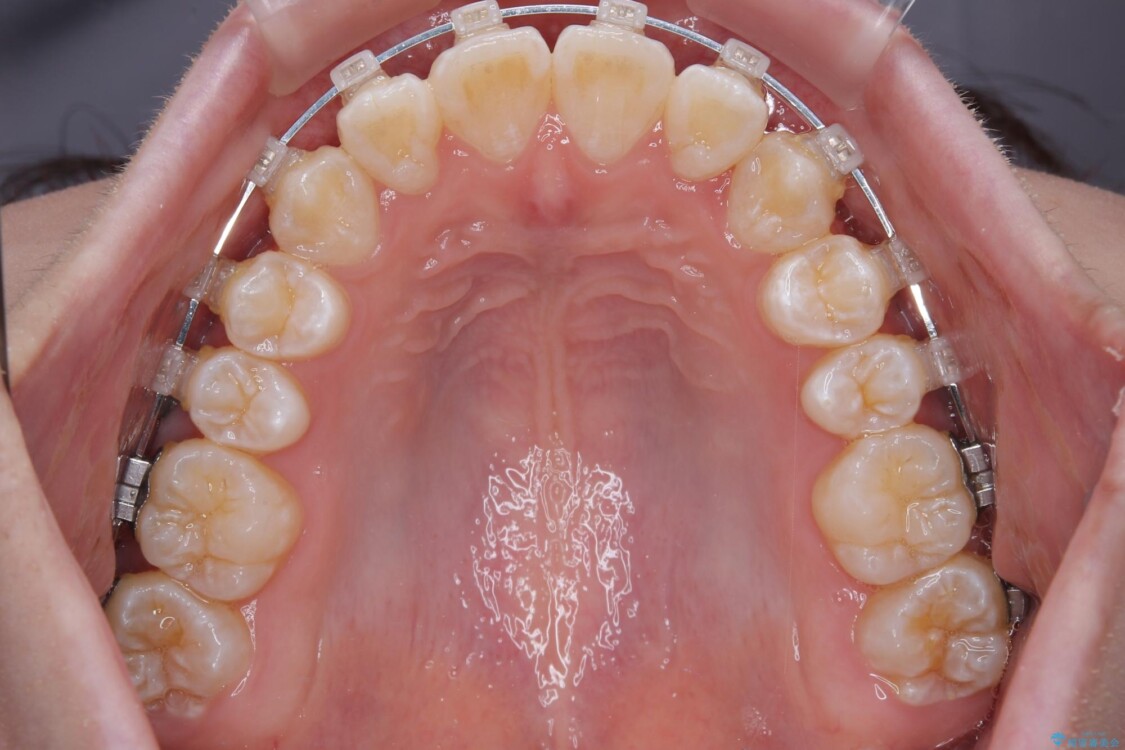

治療途中

• 【モニター】前歯のデコボコをスッキリ解消!目立ちにくいワイヤー矯正でスピーディに治療完了 治療途中画像

患者様の協力もあり、およそ1年間で治療を完了。スムーズな歯の移動を実現しました。

上下の正中(真ん中のライン)もずれることなく、バランスの取れた美しい歯並びに。笑顔に自信を持てる仕上がりとなりました。